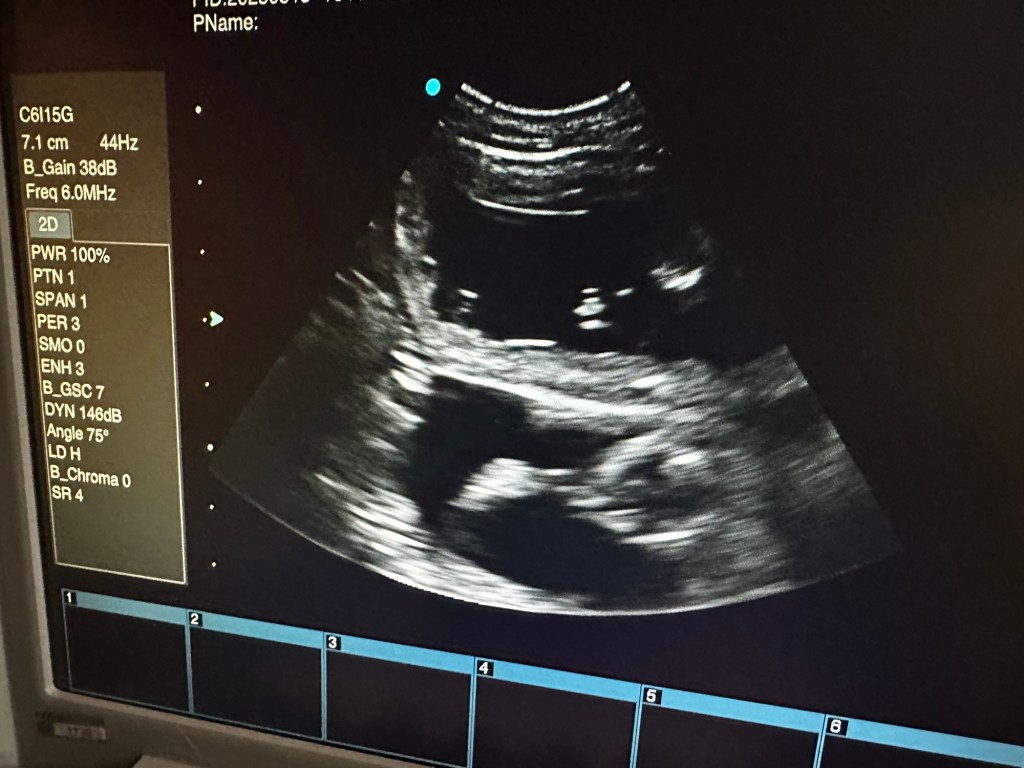

I dag har vi tatt ultralyd og begge tispene våre er drektige. Oliane med et lite kull og Naya med et stort kull. Elevene var med på ultralyd og nå er det bare å vente frem til røntgen uken før forventet termin.